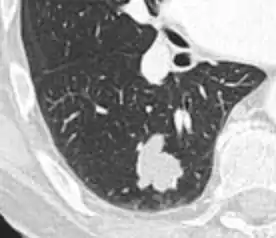

- Pleural retraction is far more common in cancers.[9] It is the pulling of visceral pleura towards the nodule.[9]

Nodule with pleural retraction.[9]

In this case, pleural retraction is seen as a triangular fat component.[9]